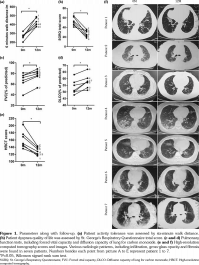

After 12 months of CYC-PFD treatment, all patients showed significant improvement in their clinical status and HRCT. The PFTs were improved or stable. All patients who received steroids were successfully maintained at 10 mg prednisone daily or less. The 6MWD showed a median increase of 52.7% (range, 34.4 to 86.3%, p<0.05). For quality of life assessment, the SGRQ total score showed a median improvement of 53.3% (range, 19.5 to 61.7%, p<0.05). The HRCT score showed a median decrease of 20.1% (range, 11.7 to 29.6%, p<0.05). Regarding lung functions, the DLCO percentage showed a median improvement of 6.3% (range, 1.7 to 16%, p<0.05) and the FVC percentage showed a median improvement of 13.4% (range, 0 to 35.9%, p<0.05) (Table 2, Figure 1a-f).

Patient 6: This patient is a 55-year-old male with more than 20-year smoking history (20 cigarettes a day on average). He was diagnosed as SS-ILD two years before, at which time he quit smoking. He was treated with prednisone (15 mg per day) and hydroxychloroquine (0.4 g per day) for over eight months. At enrolment, because of severe dyspnea, he had difficulty in talking for more than 10 minutes or climbing two flights of stairs because of dyspnea. Additionally, he had mild cough and felt severe fatigue all day. His chest HRCT showed diffused infiltration and reticular fibrosis, mostly along the peripheral area of the lungs (Figure 1f). After three months of combined treatment, he had no talking difficulties; 12 months later, he could climb five flights of stairs without dyspnea. His prednisone dose was maintained at 7.5 mg per day since the ninth month of follow-up.

Patient 7: This patient is a 63-year-old female with a 15-year smoking history (approximately seven cigarettes per day) until she was diagnosed as anti-synthetase antibody-associated ILD two years before. She was treated with azathioprine (50 mg per day) for one year. She developed dry cough three months prior to enrolment. She was first treated with 15 mg/day prednisone for two months, but her symptoms still progressed. Her dose of prednisone was increased to 60 mg per day for one month without additional improvement. At enrolment, she suffered dyspnea and dry cough, with difficulties in her daily housework. She had consolidation and ground glass opacity over almost 50% of her lung field (Figure 1f). After two months of combined treatment, she was not bothered by dyspnea or cough when doing housework or climbing three flights of stairs. After 12-month follow-up, her status remained stable with a prednisone dose at 7.5 mg per day for six months.